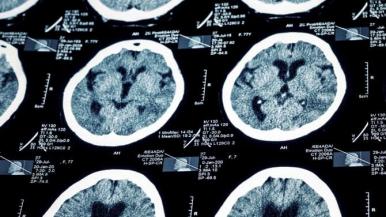

Today's imaging technology allows us to detect stroke within minutes of the first symptoms, see blood vessels in the brain that may be blocked and find out where blood is and isn't flowing.

"It’s helpful to know where blood flow is blocked when you’re considering an intervention to reopen the vessel, and it’s also helpful for us to understand the stroke mechanism, or what's causing the stroke," Conners says. "This all assists in the decision-making process and helps us improve outcomes."